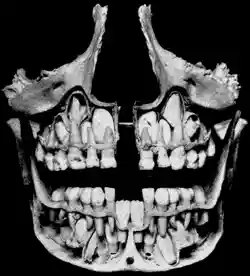

The removed bone reveals permanent teeth below the roots of primary teeth. | |

The primary dentition stage starts on the arrival of the mandibular central incisors, typically from around six months, and lasts until the first permanent molars appear in the mouth, usually at six years.[12] There are 20 primary teeth and they typically erupt in the following order: (1) central incisor, (2) lateral incisor, (3) first molar, (4) canine, and (5) second molar.[13] As a general rule, four teeth erupt for every six months of life, mandibular teeth erupt before maxillary teeth, and teeth erupt sooner in females than males.[14] During primary dentition, the tooth buds of permanent teeth develop inferior to the primary teeth, close to the palate or tongue.

The permanent dentition stage begins when the last primary tooth is lost, usually at 11 to 12 years, and lasts for the rest of a person's life or until all of the teeth are lost (edentulism). After the permanent tooth forms in the bone, it will push through under the primary tooth. The adult tooth will dissolve the primary tooth's root, making the primary tooth loose until it falls out.[8] During this stage, permanent third molars (also called "wisdom teeth") also erupt. These are sometimes extracted because of decay, pain or impactions. The main reasons for tooth loss are decay or periodontal disease.[21]